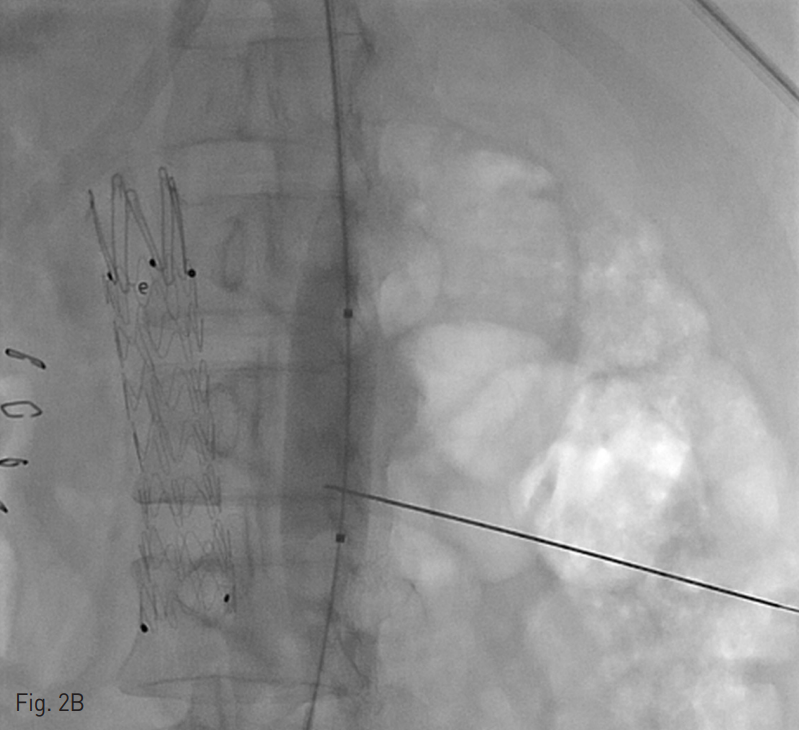

양측 내경정맥을 통한 정맥 조영술에서 상대정맥이 완전히 폐색되어 있으며 (Fig. 1A-B) 이를 대체하기 위해 우측 대퇴정맥에 투석용 카테터를 삽입하였지만 이 또한 10일 후 카테터 주변으로 혈전이 발생하였다(Fig 1C). 이어서 허리 경유 접근을 통해 투석용 카테터 삽입을 위해 하대정맥 천자를 시도하였으며 6 Fr sheath까지 들어간 후에 천자된 곳이 대동맥임을 알게 되어 대동맥에 stent-graft를 넣었다 (Fig. 2A). 투석이 급하여 일단 간정맥을 통하여 투석용 카테터를 삽입하였으나 (Fig. 1D) 이 역시 혈전으로 인한 기능 부전으로 수 차례 교환술을 시행하였다.

Fig. 2. Successful placement of translumbar tunneled dialysis catheter.

A. Through the transhepatic access, a 0.035-inch guide wire was advanced to the inferior vena cava. Note the previously inserted aortic stent graft (arrows).

B. A 16mm x 4cm balloon catheter was inflated as a puncture target, the inflated balloon catheter was success fully punctured with a Chiba nedle